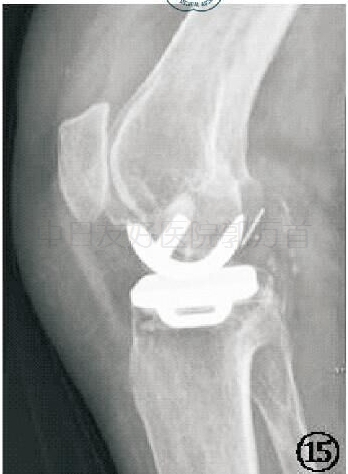

对于胫骨假体:①在前后位,假体与胫骨轴成角90°(容许5°误差)。其外侧靠近髁间嵴,内侧缘达到胫骨内侧骨皮质,并允许轻度伸出,但不要超出胫骨皮质内侧2 mm。骨—假体界面应该显示出薄层连续骨水泥层并向骨质渗透几毫米。骨水泥在外侧面及龙骨周围渗入的范围比在中间渗入的更深。②在侧位,胫骨假体需要后倾7°,即假体水平面向后下倾斜与胫骨纵轴成7°角(容许5°误差)。假体后缘应该达到后侧皮质,但悬出不超过 2 mm。若悬出过多,可能意味着胫骨假体龙骨槽开槽时损害了胫骨后侧骨皮质。

胫骨假体前后位、侧位示意图